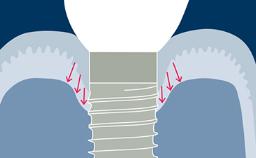

Um histórico completo e exame clínico são essenciais ao planejar a substituição de dentes por implantes dentários. Antes da cirurgia, as avaliações clínicas e radiográficas específicas do local devem ser cuidadosamente conduzidas. Essas avaliações fornecerão as informações necessárias para formular um plano de tratamento detalhado e individualizado, capaz de atender às expectativas realistas do paciente. Portanto, um exame abrangente é obrigatório para antecipar quaisquer complicações que possam resultar do tratamento. Neste módulo, discutiremos os exames específicos da região recomendados e sua relevância para pacientes que consideram substituir um ou mais dentes por implantes dentários. As avaliações específicas da região que serão discutidas neste módulo são o espaço restaurador e suas características, fatores anatômicos e tecidos duros e moles, incluindo quaisquer patologias na área.